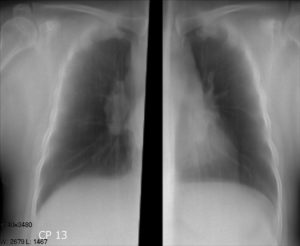

Узнать, что сердце расширило свои границы можно при обследовании методом УЗИ, рентгенографии, ЭхоКГ или МРТ. Например, рисунок №1 представлен в виде снимка флюорографии. Тень, отмеченная на изображении, говорит о расширении тени органа.

Рис.1. Флюорография расширенного сердца.

Рисунок №2 позволяет визуально сравнить нормальное состояние предсердий и желудочков, и момент, когда орган расширил свои границы.

Рис.2. Сравнение нормального и расширенного сердца.